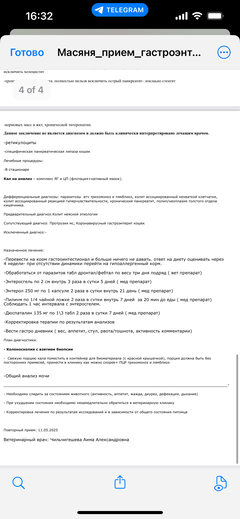

Ярко выраженная болезненность в области крестца, на обезболе полегче. По результатам приема невролога проведена миелография - множественная компрессия, возможно опухоль, возможно грыжа, нужно удалять...

Помогите нам с Масяней пожалуйста